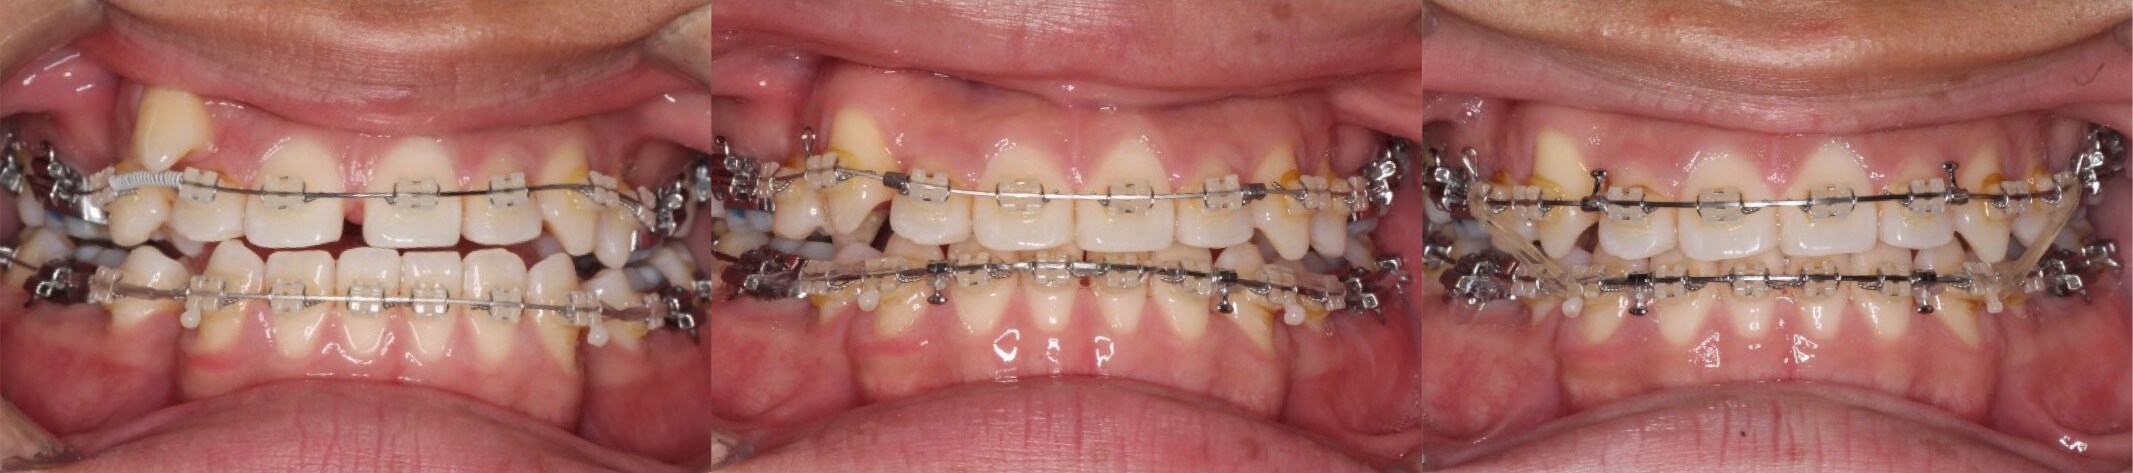

高校生男性・唇側矯正装置・小臼歯4本抜歯

<顔のビフォーアフター>

<症例概要>

主訴:受け口

年齢・性別:高校生男子

住まい:千葉県八千代市

症状:反対咬合・叢生

治療方針:抜歯空隙閉鎖

治療装置:唇側矯正装置

抜歯:上第二小臼歯・下第一小臼歯(計4本)

治療期間:2年9か月

リテーナー:上下プレートタイプ+クリアタイプ

治療費用:935,000(税込)

代表的副作用:痛み・治療後の後戻り・歯根吸収・歯髄壊死・歯肉退縮

男性の場合は下あごの成長期間が長いため、受け口の本格治療は、17歳くらいから開始した方が良いと言えます。でこぼこもあったため、小臼歯抜歯も併用して矯正治療を行いました。下の前歯が後ろに引っ込み治療後の横顔はスッキリしました。